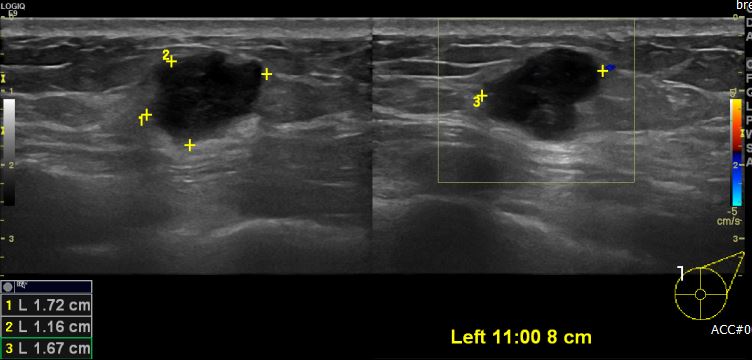

상기 환자 좌측유방에 만져지는 멍울로 내원하신 60대 여성분으로 유방 초음파상 좌측

11시 방향에서 8cm 떨어진 거리에 의심스러운 멍울 조직검사 시행하여

좌측 침윤성 유관암 진단 되었습니다.